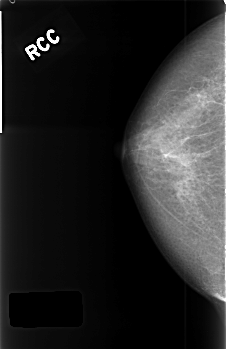

C_0406_1.RIGHT_CC

RIGHT_CC LINES 4528 PIXELS_PER_LINE 2928 BITS_PER_PIXEL 12 RESOLUTION 50 NON_OVERLAY